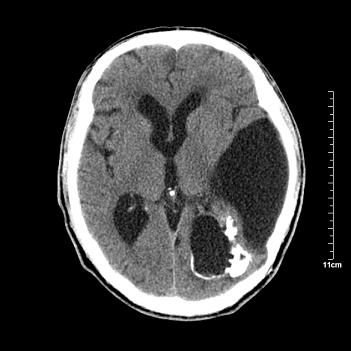

男性患者,72岁,近两天头晕来我院就诊。 因患者血压太高而未做增强,建议病人去市医院做mri检查。等得到mri随访结果再公布给大家。 测及左颞顶枕叶病灶ct值分别为5hu 30hu 729hu。

考虑左侧颞顶枕叶少突胶质细胞瘤。 今天随访患者手术病理结果 病理回报为胶质瘤2级 钙化

左侧颞顶枕叶大片状低密度影,呈均一水样密度,边界清楚,病灶边缘不规则片状钙化,左侧脑室后角扩大,中线结构未见移位,综合来看不像肿瘤,软化灶,钙化不好解释

左侧颞顶枕叶巨大囊性病灶,灶内见小片实性区且灶内及灶周围大量团块状钙化影,灶周水肿少.左侧室枕角内见环形钙化,可见较清晰前壁,钙化与室壁似有间隙.

囊变明显,钙化明显,部分实性组织,轻度占位,左侧脑室受压---考虑 少突胶质细胞瘤,畸胎瘤,寄生虫病

今天追踪患者家属手术病理结果 病理回报为胶质瘤2级并钙化

病理回报为胶质瘤2级并钙化